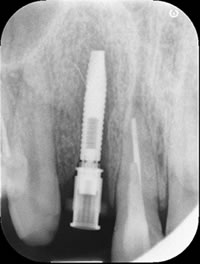

埋入後のレントゲン像です。前歯のインプラントは通常のレントゲンの他に、術後のCTが必要になります。